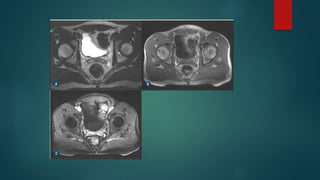

ABSCESSO

 Normalmente decorre por manipulação cirúrgica ou extensão

direta de abscesso prostático .